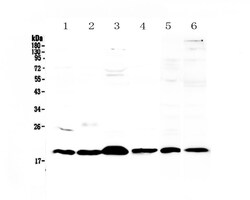

Reconstitute with 0.2 mL of distilled water to yield a concentration of 500 μg/mL. Positive Control - WB: mouse stomach tissue, mouse spleen tissue, mouse thymus tissue, mouse small intestine tissue, rat thymus tissue, human placenta tissue. IHC: mouse spleen tissue, mouse thymus tissue, rat spleen tissue.

| ELISA, Immunohistochemistry (Paraffin), Western Blot | |